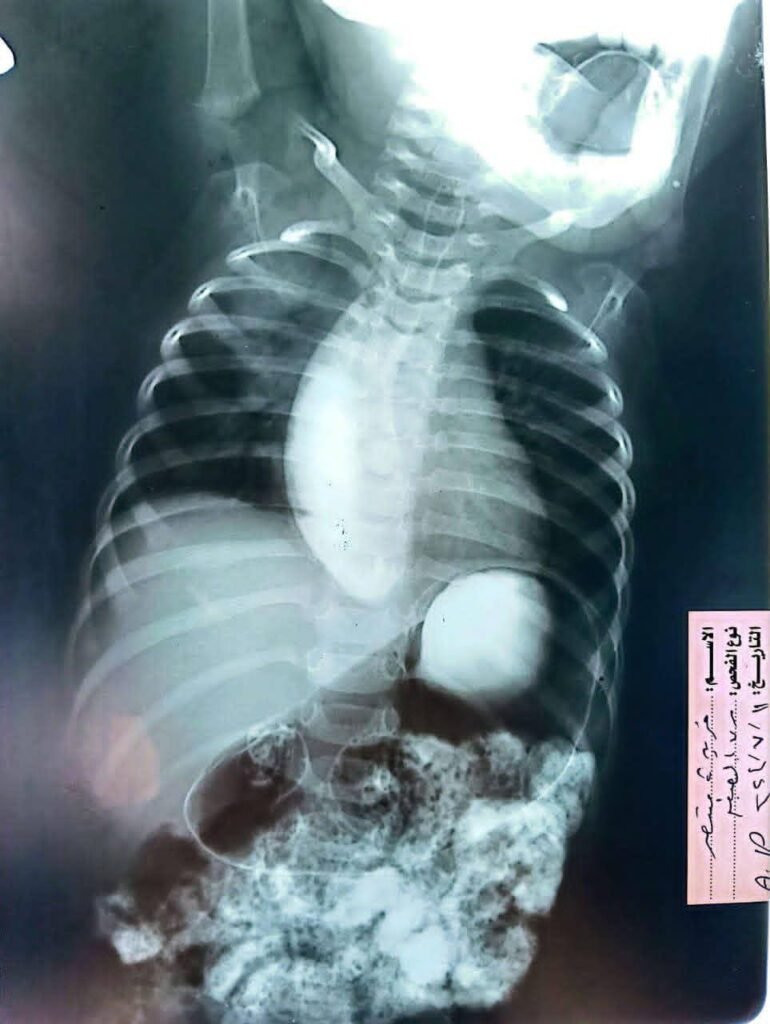

أجرى قسم جراحة الأطفال بالتعاون مع قسم الجهاز الهضمي والكبد بمستشفى سيد جلال الجامعي بطب الأزهر عملية تدخل علاجي دقيق بتقنية شق عضلة المريء بالمنظار (Per Oral Endoscopic Myotomy – POEM) لطفلة تبلغ من العمر عامين فقط وبوزن ٩ كجم؛ حيث عانت الطفلة من قيء مستمر، وصعوبة شديدة في البلع، وتأخر ملحوظ في النمو إلى أن تم حجزها والاعتناء بحالتها بقسم جراحة الأطفال بمعرفة د/أحمد أبو الحسن، صاحب الدراسة البحثية لعلاج حالات أكاليزيا الأطفال بالمنظار، تحت إشراف أ.د /إبراهيم جمعان، رئيس وحدة مناظير جراحة الأطفال، ثم تم إجراء العملية بوحدة مناظير الجهاز الهضمي بقسم الكبد والجهاز الهضمي، بالتعاون مع فريق قسم جراحة الأطفال، والتي استغرقت نحو ٣٠ دقيقة فقط، بنجاح تام دون حدوث أي مضاعفات أثناء أو بعد إجراء العملية، مع تحسن ملحوظ وسريع في البلع، وخروج الحالة بسلام من قسم جراحة الأطفال بعد التأكد من نجاح التدخل واستقرار الحالة العامة.

وتُعد هذه الحالة Case Report علميًّا؛ حيث تُصنف باعتبارها من الحالات النادرة التي يتم فيها تطبيق تقنية POEM لطفل يقل عمره عن ٣ سنوات ووزنه أقل من ١٠ كجم، وهو ما يمثل إضافة علمية وطبية متميزة باسم مستشفيات جامعة الأزهر بما يعزز من مكانة الجامعة إقليميًّا ودوليًّا في مجال مناظير الجهاز الهضمي العلاجية المتقدمة والتدخلات فائقة الدقة بالمنظار.